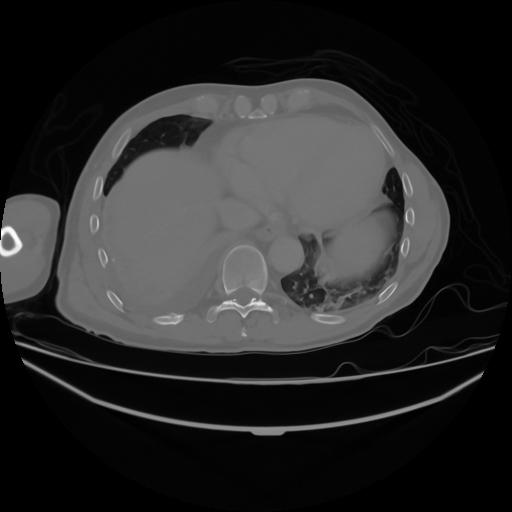

4 CUERPO,CE,Axial,3.0,CUERPO,,